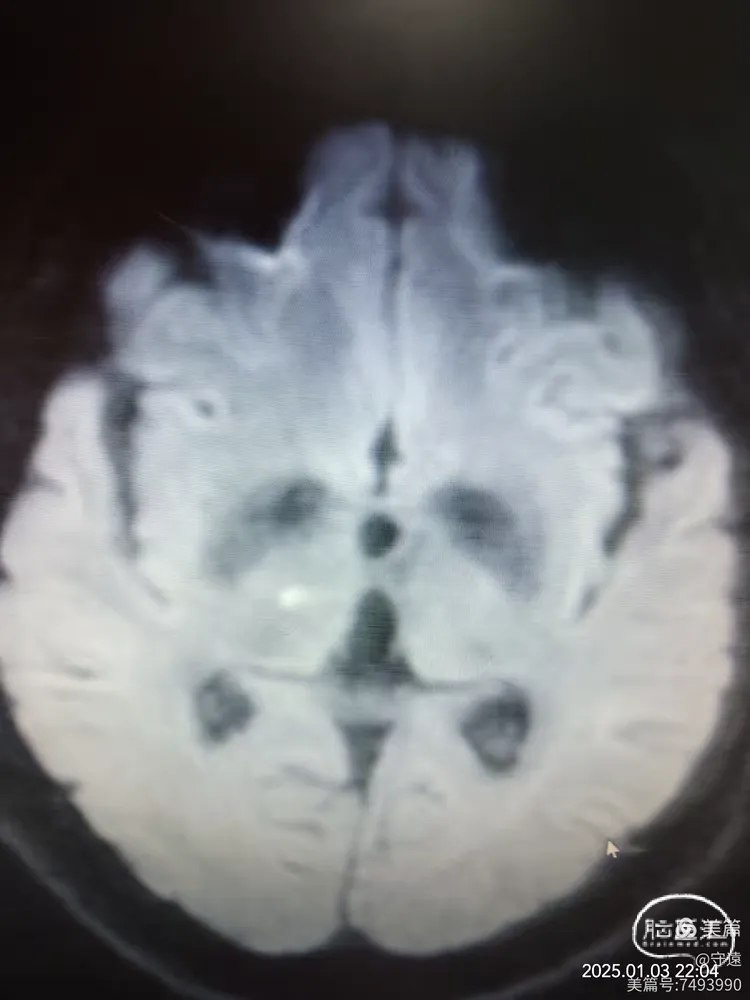

核磁显示:双侧桥臂,右侧丘脑梗塞。

DwI示双侧桥臂高密度影

右侧丘脑梗塞